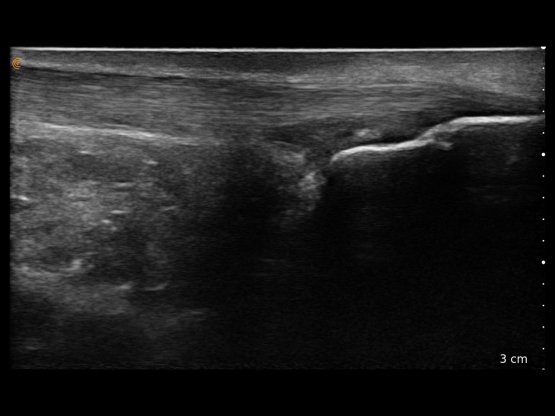

Mittels Ultraschall können sowohl die Weichteile als auch oberflächliche Bereiche der Knochen eines Gelenks dargestellt werden. Veränderungen von Sehnen, Muskeln, Nerven und Blutgefäßen können mit unseren hochauflösenden Geräten hervorragend abgebildet werden. Die Arthrosonographie (Gelenkultraschall) zählt zu den nicht invasiven, das heißt nicht in den Körper eindringenden, diagnostischen Verfahren. Die eingesetzten Schallwellen sind für den menschlichen Körper nicht schädlich. Die Untersuchung mit Ultraschall ist außerdem schmerzfrei. Bei einer Sonographie wird ein Schallkopf auf die Haut aufgesetzt. Ein Kontaktgel sorgt für optimale Bildqualität in HD-Auflösung. Auf einem Monitor werden die Gewebe- und Gelenkstrukturen unter der Haut dargestellt.

Im Gegensatz zum Röntgen, das die Weichteile nicht detailliert darstellt, kann man mit der Arthrosonographie alle nichtknöchernen Veränderungen am Gelenk und am sonstigen Bewegungsapparat sehr gut beurteilen (Muskulatur, Sehnen, Gelenkinnenhaut, Schleimbeutel, Gelenkerguss). Auch die Knochen selbst können insbesondere in ihren Gelenkkomponenten gut dargestellt werden. Lediglich eine Beurteilung der internen Knochenstruktur ist aufgrund der Reflexion der Schallwellen an der Knochenaußenseite nicht möglich. Außerdem kann man mit der Arthrosonographie die genannten Strukturen und vorhandene Veränderungen auch dynamisch untersuchen. Beispielsweise ist es so möglich, eine Sehne oder auch ein ganzes Gelenk in Bewegung darzustellen. Befunde können auch mit der Gegenseite verglichen werden.

Die Nutzung der Sonographie ermöglicht u.a. die äußerst präzise Planung und Durchführung einer Injektion (große Gelenke wie Knie und Schulter) oder auch Infiltration (Sehnen und z.B. Facettengelenke der Wirbelsäule, ISG). Sowohl bei der akuten Schmerzbehandlung, als auch bei die Regeneration unterstützenden Behandlungen wie der Hyaluronsäuretherapie setzen wir die sonographische Untersuchung, Markierung und postinterventionelle Kontrolle als zuverlässiges Werkzeug ein. Dies vermeidet insbesondere unnötige Fehlpunktionen und damit verbundene Beschwerden und verbessert den Therapieerfolg nachweislich.